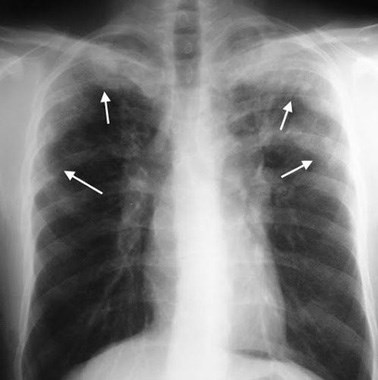

(vi) X-quang phổi cho thấy các đám mờ di động ở phổi. Chụp X-quang phổi cho thấy có đám mờ di chuyển so với vị trí trước đó 12-20 ngày. Tuy nhiên, tổn thương phổi quan sát được trên phim có thể biến mất hoàn toàn trong vòng 2-4 tuần. Đối với bệnh tăng BCAT ở phổi do thuốc, bất thường trên X-quang sẽ giải quyết hoàn toàn vài tuần sau khi ngừng dùng thuốc nghi ngờ;

|   Hình 1. Chụp X-quang phổi ban đầu của một bệnh nhân nam 54 tuổi, cho thấy đám mờ (mũi tên) trên thùy giữa của phổi phải   |    Hình 2. X-quang phổi cho thấy đốm mờ di chuyển theo thời gian khi bệnh nhân chưa điều trị   |